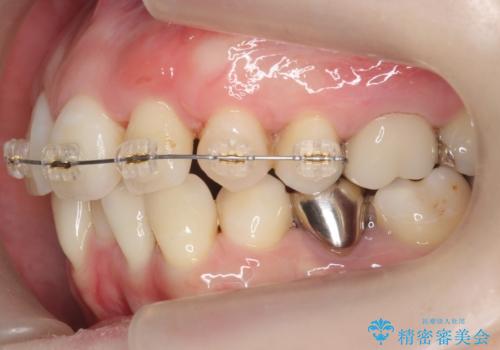

上にはワイヤー部分矯正を行った後、インビザラインでマウスピース矯正を行っています。

八重歯の部分は抜歯し、奥に入っていた前歯を前に移動させました。

犬歯を抜いたとしても、矯正治療を短期間で終わらせて歯に負担がかからないようにし、虫歯治療その分しっかり行うのもメリットがあるのではないかと思います。